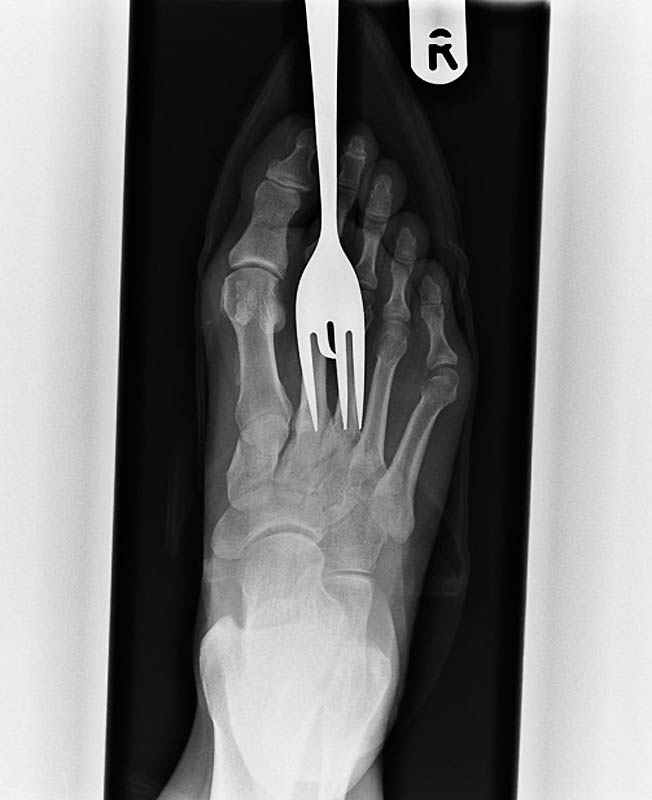

3. Старинный рентгеновский снимок ступни солдата англо-бурской войны (1899-1902) с огнестрельным ранением. Пуля застряла в плюсневой кости между большим и вторым пальцами.